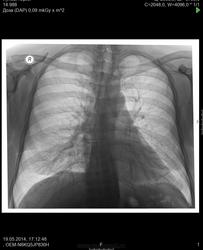

Усиление легочного рисунка в S5 справа

В анамнезе - пневмония 3 года назад)) Усиление легочного рисунка в S5 справа

Думаю, остатки ранее перенесенного процесса.

Мне кажется вообще норма+ разворот

Длоя нормы как-то уж очень тяжисто

Поствоспалительный пневмофиброз,если нет клиники.

Выставить пневмофиброз и по данным снимкам можно. Это круто, конечно. Тем паче, без КТ, без архива... Тем паче что его там и нету...